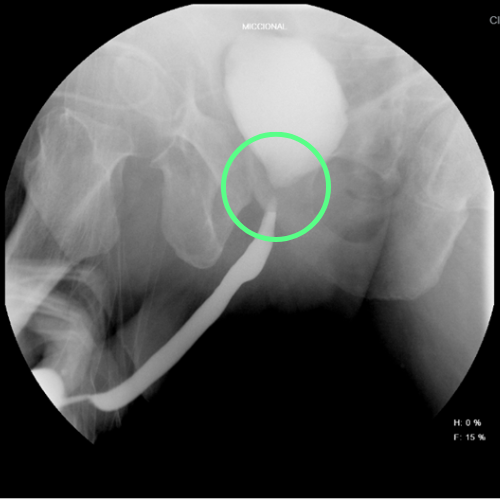

Imagen de cistouretrografía con referencias que permiten identificar un segmento uretral con calibre normal y uno con calibre reducido.

Cistouretrografía que revela una estenosis de uretra. El asterisco (*) marca una porción de uretra con calibre normal, mientras que el círculo un segmento más estrecho.